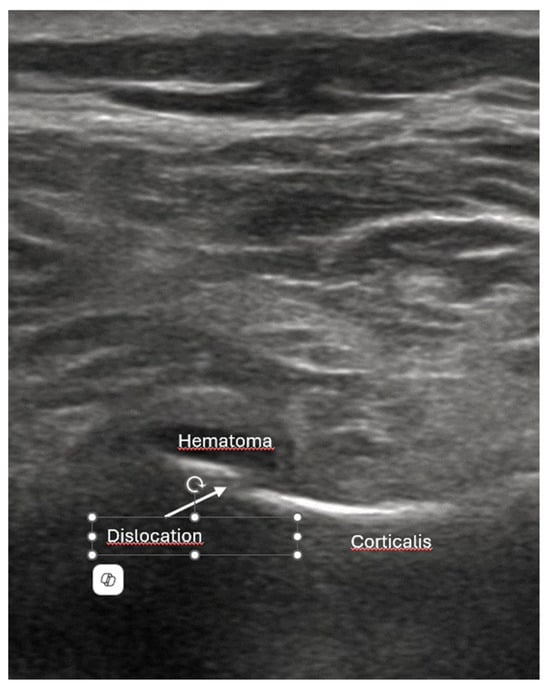

- Dislocation: misalignment of bone fragments, visible as separation or shift from their normal anatomical position.

- Local hematoma or soft tissue edema: fluid collections or increased echogenicity near the fracture site indicating bleeding and inflammation.

- Quick exclusion of fractures in shoulder dislocations for timely reduction (Figure 13).

- Recommendation 6: Ultrasound should be integrated into the assessment and management of shoulder injuries, including proximal humerus fractures, shoulder dislocations, and post-relocation maneuvers, both prehospitally, in emergency departments, and other acute care settings.

- Example: Suspected left shoulder dislocation